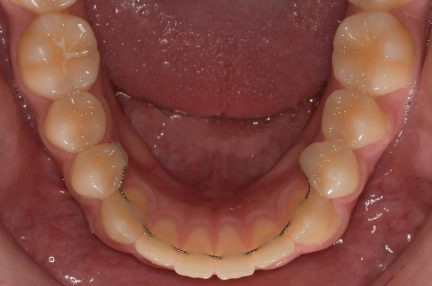

État final

- Arches alignées et coordonnées

- Alignement des deux arcades par dérotation

- Forme de l'arcade améliorée

- Des arcades harmoniques ont été obtenues

Contention

- Maxillaire: Vivera retainer

- Mandibulaire: Vivera retainer